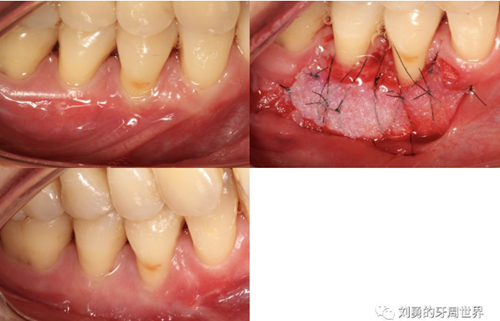

對于需要進(jìn)行根面覆蓋的手術(shù),移植瓣需要縫合固定到CEJ冠向1mm左右的位置。如下圖:

比如下面兩張圖就分別是縫合和剪掉的方法:

第五個要說的改良就是受區(qū)半厚瓣的改良,一種使用手術(shù)刀翻開半厚瓣,暴露骨膜床的方式,該方法操作起來困難尤其是后牙區(qū)域,另外一種方式是用高速手機(jī)金剛砂車針大量噴水磨除受區(qū)表皮組織的方法來暴露骨膜床,該方法操作簡單粗暴,出血多。如下圖: